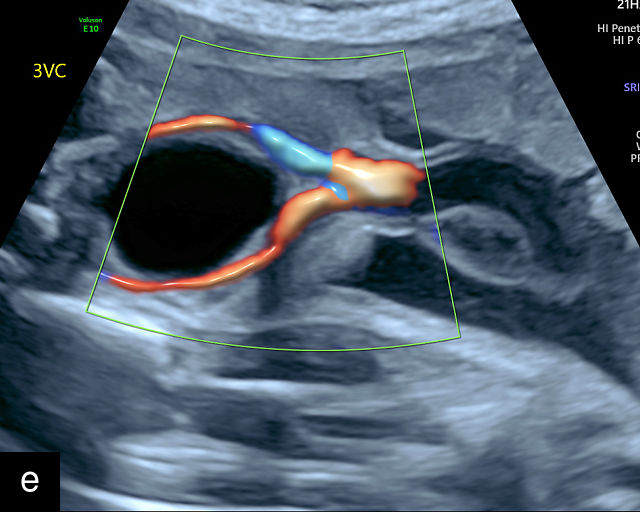

21

(a) Type-1 vasa previa. Photograph after delivery showing the umbilical cord inserting into the membranes through which unprotected fetal vessels run to insert into the placental edge. (b) Type-2 vasa previa. Photograph after delivery showing bilobed placenta with unprotected fetal vessels running though the membranes between the lobes. (c) Type-3 vasa previa in a twin pregnancy. Photograph after delivery showing unprotected vessels running through the membranes from one edge of the placenta to another (arrow). (d) Transabdominal grayscale ultrasound of the lower uterine segment showing a linear hypoechoic structure (fetal vessel) running over the cervix (c) indicating vasa previa (Type 2). b, bladder; h, fetal head. (e) Transabdominal color Doppler ultrasound of the lower uterine segment showing fetal vessels (arrow) running over the cervix (c) indicating vasa previa (Type 2). (f) Transabdominal ultrasound with color flow and pulsed-wave Doppler of the lower uterine segment showing a fetal vessel running over the cervix (c) indicating vasa previa (Type 2). Pulsed-wave Doppler demonstrates an umbilical arterial waveform. (g) Transvaginal grayscale ultrasound with showing a Type-2 vasa previa. There are two placental lobes, an anterior (a) and a posterior (p) lobe. There is a linear and circular hypoechoic structure (arrow) running over the cervix (c) between the lobes. (h) Transvaginal grayscale ultrasound image of vasa previa. A hypoechoic linear structure (arrow) is seen running through the membranes over the cervix (c). h, fetal head. (i) Transvaginal grayscale ultrasound of vasa previa. Hypoechoic circular and linear structures are seen close to the internal os. (j) Transvaginal color Doppler ultrasound image of vasa previa. A fetal vessel is seen running through the membranes over the internal os (arrow) of the cervix (c). h, fetal head. (k) Transvaginal ultrasound with color Doppler showing a Type-2 vasa previa. There are two placental lobes, an anterior and posterior lobe (pl). Fetal vessels run over the cervix between the lobes. (l) Transvaginal color flow ultrasound with pulsed-wave Doppler image of vasa previa. Color Doppler shows flow through the vessel and pulsed-wave Doppler shows a fetal umbilical venous waveform. (m) Transvaginal color ultrasound with pulsed-wave Doppler image of vasa previa. Color flow Doppler shows flow through the vessel and pulsed-wave Doppler shows a fetal umbilical arterial waveform. (n) Transvaginal three-dimensional ultrasound with color Doppler image of vasa previa. h, fetal head; c, cervix.

12